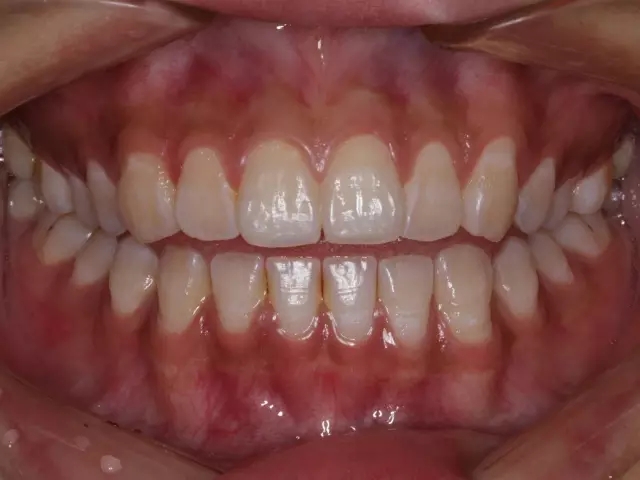

第一,“建立了咬合關系”可以不拔?

正位萌出到位,在牙尖交錯位建立咬合關系,只是一個靜態(tài)的狀況??陬M系統(tǒng)的功能要靠運動來實現(xiàn),而一旦動起來,很多“看”似建立了正常咬合關系的智齒很可能會造成咬合干擾,給整個口頜系統(tǒng)帶來傷害。

這樣 “萌出到位有咬合” 的智齒應該 拔掉